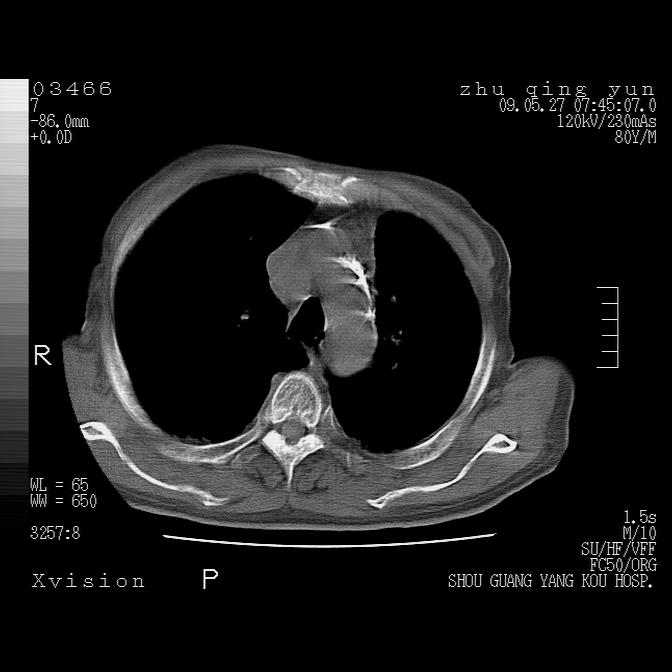

病人男性,年龄80,气喘来院,其他病史不太详细,1月前有过恶心,呕吐,在当地人民医院做过钡餐,诊断胃炎,

1)考虑左肺中央型肺癌并阻塞性肺炎,后下纵隔受侵伴纵隔淋巴结转移。2)双侧少量胸腔积液,胸膜增厚。3)心包积液。

1)考虑左肺中央型肺癌并左肺下叶阻塞性肺炎、不张;左胸膜腔积液、心包积液、纵隔淋巴结转移;癌肿累及左心房。2)左心室大。冠状动脉壁钙化斑。